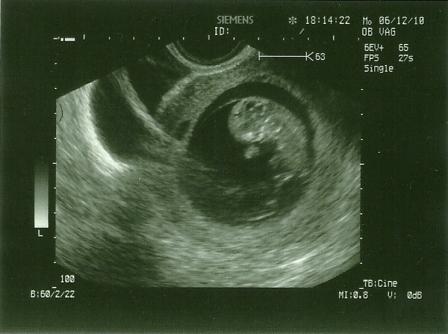

Jövök máris a képekkel!

Szemből: (a feje mellett a két kis folt a kezecskéi, alul pedig éppen összezárva a talpacskák)

Kép

Oldalról:

judit0713